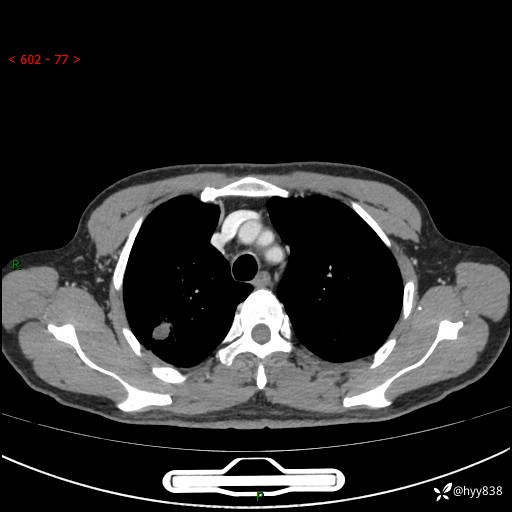

69岁/男,发现肺部病变6天。该有的征象都有,肉芽肿 VS 肿瘤,一念之间---(有结果)

主诉:发现肺部病变6天。

现病史:患者6天前于我院泌尿外科住院,住院期间行胸部CT检查,提示“肺部病变”,患者无畏寒、发热、盗汗、咳嗽、咳痰、咯血、胸痛、呼吸困难,无反酸、腹痛、腹泻、头痛、头晕等不适。未予特殊处理,现为进一步诊治,门诊以“肺肿物”收入我科。 患者本次起病以来,精神食欲尚可,大小便正常,体力及体重无明显变化。

胸部CT平扫+增强